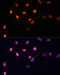

KI-67 antibody, FNab09788, FineTest, Immunofluorescence image

IF